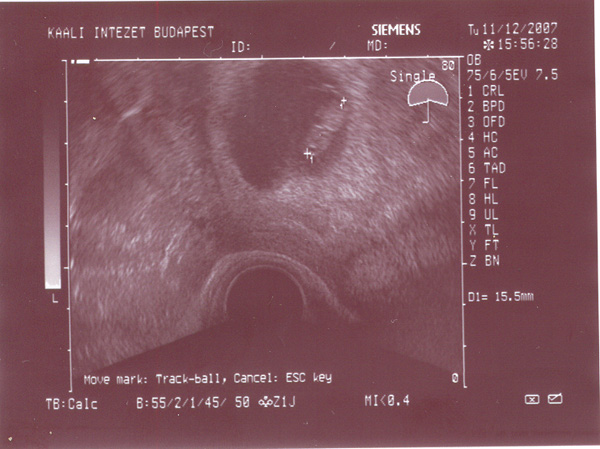

A pici rengeteget mozog, karacsony utan kell mennem egy csomo vizsgalatra ami a szüleshez kell majd, aztan januar elejen megyünk majd az orvoshoz, akkor töltöm a 37. hetet.

Kicsit aggodom, hogy megfordult -e mar, sajnos fogalmam sincs rola de remenykedem...

ez pedig Davide legujabb ajandeka: